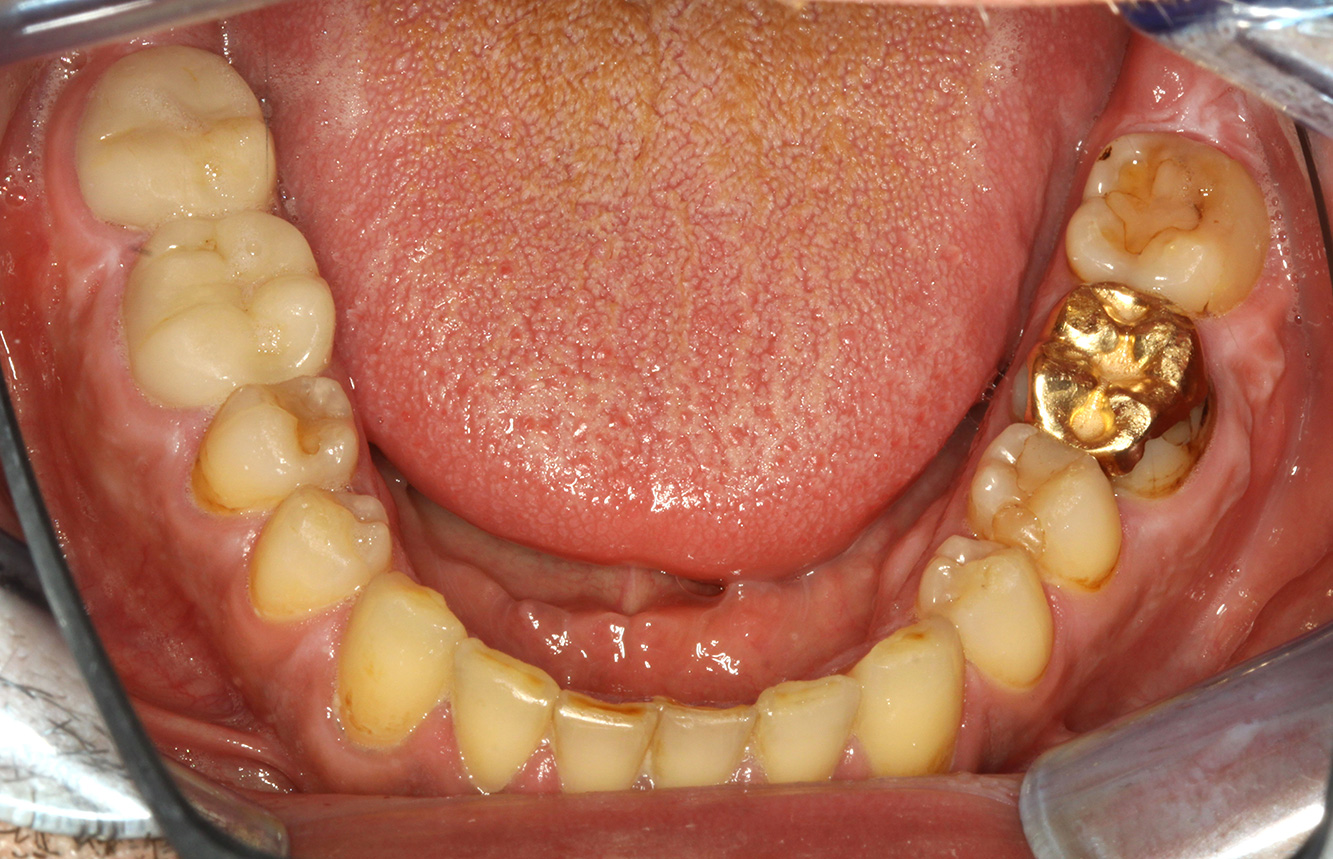

The (orally) healthy patient with implants

In the medical history, the 55-year-old patient states that he has no systemic disease and is not taking any medication. The patient’s lifestyle is similarly unremarkable. The patient has a few tooth restorations and two implants (2nd and 4th quadrants). On the basis of current findings, gingivitis is identified in an otherwise stable periodontal condition on the reduced periodontium (stage III, grade A). more